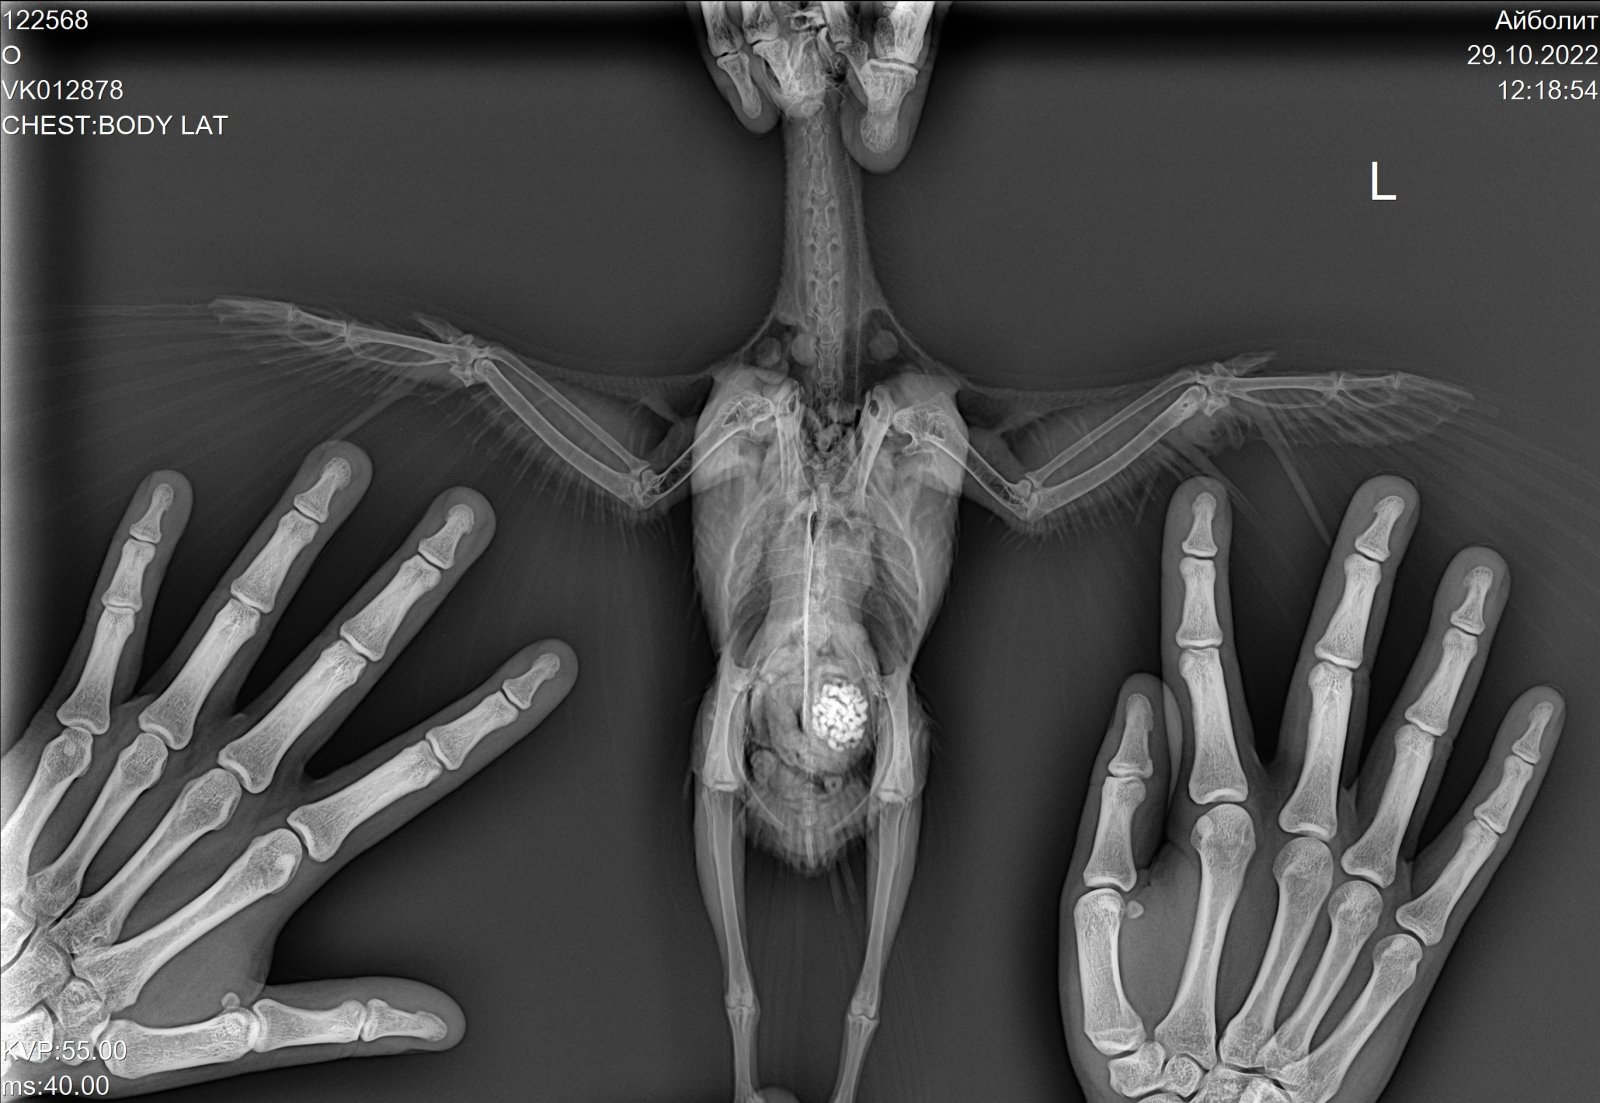

Tanya857 Опубликовано 29 октября, 2022 Автор #86 Опубликовано 29 октября, 2022 Добрый день!Шишка у Петьки отсохла и отвалилась.Летает он сейчас уже очень хорошо,залетает спокойно и на шкафы.Съездили к орнитологу сегодня,устал бедный после такой долгой дороги,но вёл себя на удивление хорошо.Крылышки осмотрели,сделали рентген.Перелома нет,только травма крыла.Ципрофлоксацин не стали менять,единственное сказали разводить немного по-другому 1/2 табл развести на 2,5 мл воды,и внутрь давать по 0,15 мл.Вместо Пимафуцина назначили Флуконазол(1/10 капсулы 2р в день). И ещё в течении 3х дней суспензию «стоп-кокцид» @Анна1972 Спасибо!Поняла?Поищу лучше как у вас силимар, может тоже будет сам клевать. По ципрофлоксацину постараюсь соблюдать интервал. 2